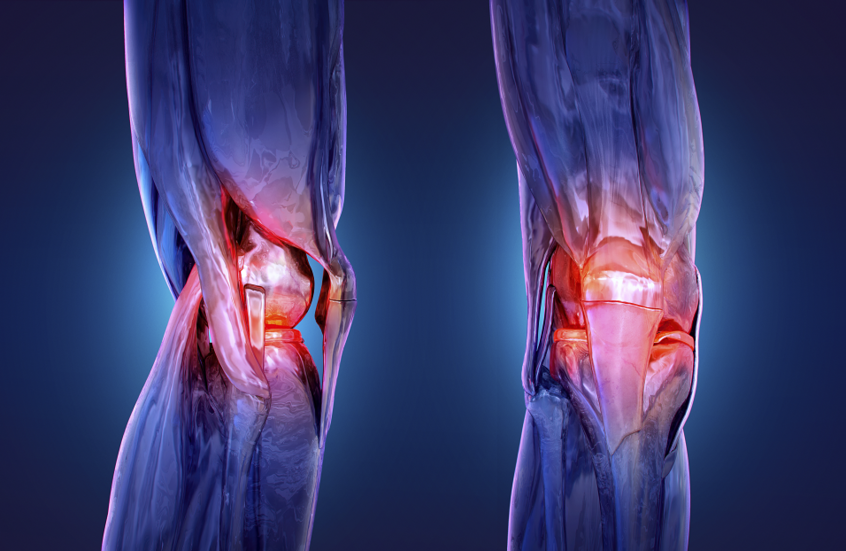

القرفة تعالج التهاب المفاصل الروماتويدي

حصل العلماء الروس على شكل جديد من «السينامالدهيد» الذي يشكل أساساً لدواءٍ لعلاج التهاب المفاصل الروماتويدي. ويعتبر أول دواء تكنولوجي حيوي لعلاج التهاب المفاصل الروماتويدي، وابتكره خبراء مجموعة شركات R-Pharm وحصل على شهادة «صنع في روسيا». والتهاب المفاصل الروماتويدي مرض شديد...